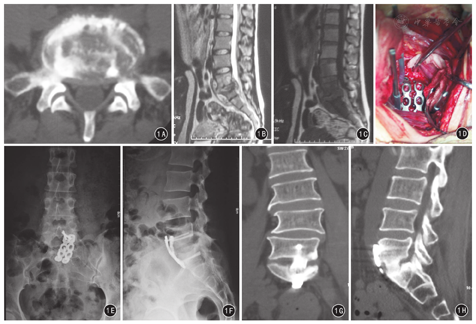

30例患者手术均顺利完成。术后所有患者病理检查结果为结核病变。1例患者因髂血管位置低,术中髂血管损伤,术中予以缝补;其余均无大血管、输尿管、神经等损伤。术后患者伤口均一期愈合,无窦道形成,男性无逆行性射精及勃起功能障碍等并发症。30例患者均获随访12~36个月,平均18个月。末次随访时30例患者均未出现内固定松动、断裂及移位情况,均获得骨性融合;根据Macnab疗效标准,评定优20例,良8例,中2例,优良率为93.3%。术后3个月及末次随访时红细胞沉降率、C反应蛋白、VAS评分和ODI均较术前明显下降,差异均有统计学意义(P值均<0.01);但末次随访与术后3个月比较,各项观察指标变化差异均无统计学意义(P值均>0.05)。见表1。典型病例见图1。

全身麻醉。取头低足高Trendelenburg位。根据X线上髂嵴与病灶节段的关系取下腹部正中切口或旁正中切口。沿腹直肌外侧缘作钝性分离至腹膜外脂肪,钝性分离腹膜及腹壁肌层。将腹膜连同腹腔内脏器牵向一侧,湿纱布保护下用S拉钩牵引,寻找左右髂动脉分叉部位,仔细分离髂血管在腰骶椎前方的粘连组织,并结扎影响显露的小分支,肾盂拉钩将髂血管拉向一侧,充分显露腰大肌及病变椎体。注射器穿刺确认椎旁脓肿后,纵行切开脓壁,吸除脓液,彻底清除椎旁、腰大肌及髂窝内干酪样组织、死骨,以及坏死的椎间盘组织,刮匙刮除脓腔壁肉芽组织。凿除或刮除病变椎体的上位椎体下方和下位椎体上方的软骨终板及部分椎体。若病灶侵犯椎管,则清除椎管内脓肿,行椎管彻底减压。过氧化氢溶液及生理盐水反复冲洗,直至冲洗液清亮。彻底止血,同时予以异烟肼300 mg冲洗,将混有2 g链霉素的明胶海绵填塞病灶处。更换手术器械及手套,取皮质骨自体髂骨块,根据植骨位置及大小修剪合适大小后植入,取重建钛板按腰骶椎生理曲度塑形,确保钛板与腰骶椎紧密贴附,在植骨块上下两个椎体分别置入金属接骨螺钉。C形臂X线机透视证实内固定物植入理想。彻底止血后,于病灶最底层常规放置引流管,逐层关闭手术切口。